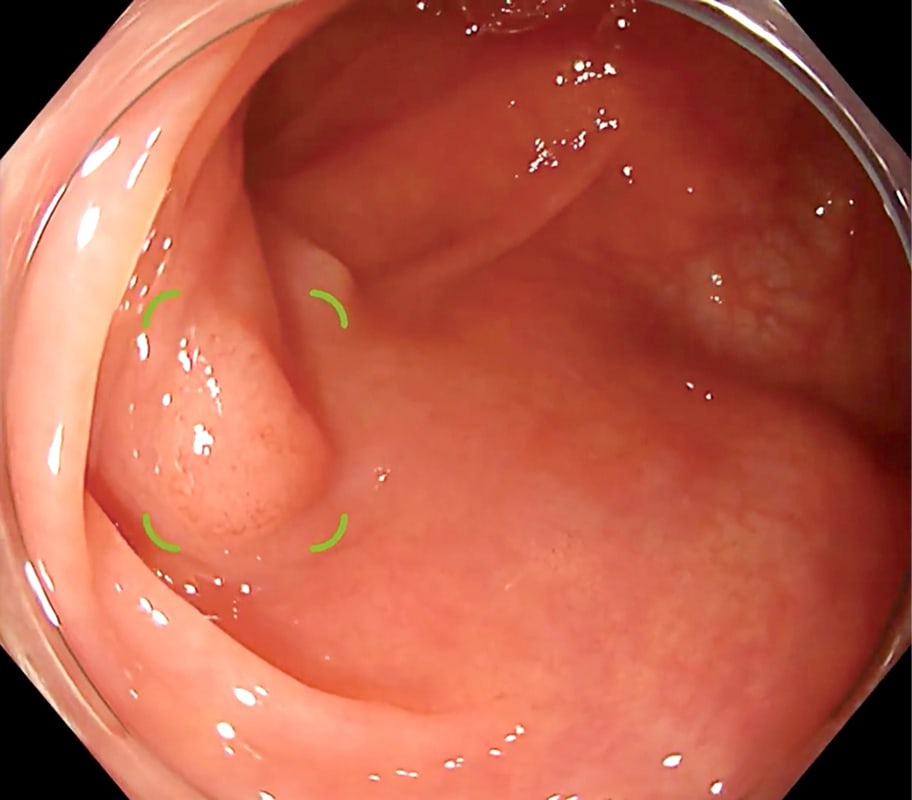

大腸ポリープ候補*を検出し、

大腸内視鏡検査を支援する

大腸内視鏡検査中に通常白色光モードにおいて入力された大腸内視鏡画像情報から、大腸ポリープ候補を検出することが出来ます。検出した場合には、メイン画像の四隅を囲むアラート枠を表示した後、ポリープ候補領域の四隅を囲む矩形を表示します。

* 隆起型及び表面型(表面隆起型)